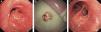

Se describe el caso de un varón de 65 años con disnea de esfuerzo de 2 meses de evolución. En la TC torácica se observó la presencia de una masa que ocupaba el bronquio superior izquierdo. Al realizar la broncoscopia se detectó un tumor rosa, moruloide muy vascularizado, que obstruía parcialmente el orificio bronquial del lóbulo izquierdo y se consideró una neoplasia maligna (fig. 1A). Al retirar la superficie del tumor, se halló una masa pediculada, dura y amarillenta con apariencia de palomitas de maíz. No fue posible extirpar la masa con pinzas, por lo que se optó por la crioterapia, mediante la cual se resecó la masa íntegramente y se resolvió la obstrucción (fig. 1B). No se produjeron complicaciones, y el análisis histopatológico del tumor confirmó el diagnóstico de condroma. Al repetirse la broncoscopia 8 semanas más tarde, se observó que el bronquio superior izquierdo no estaba obstruido y que la mucosa bronquial del lecho quirúrgico era normal (fig. 1C).